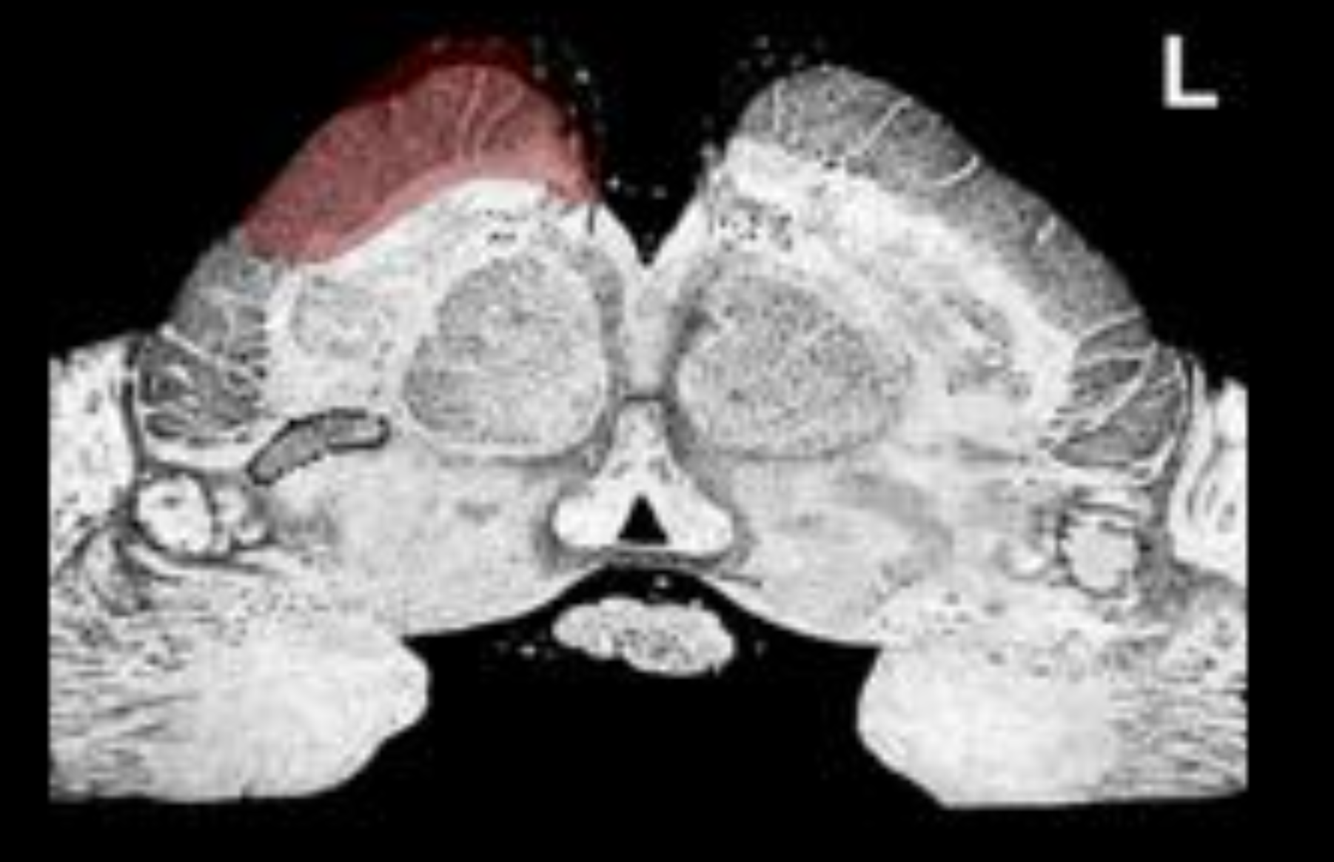

What is the name/location/results of the condition caused by a lesion in the shaded area?

Medulla, mid olive.

Right alternating hypoglossal hemiplegia

1) Destruction of the hypoglossal nerve results in ipsilateral paralysis of the muscles of the tongue, and atrophy of the ipsilateral muscles of the tongue

2) Destruction of the corticospinal tract at this level results in contralateral spastic hemiplegia